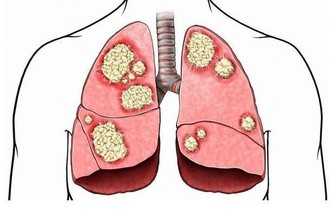

腫瘤阻塞,當腫瘤長至相當體積,或浸潤腸壁肌層時,

可引起腸管狹窄,腸腔變小,腸內容通過受阻。